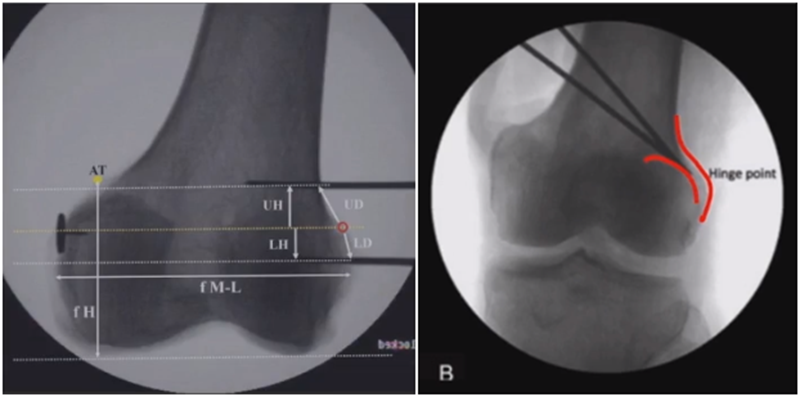

合页点的选择与HTO一样,通常需要尽可能接近畸形部位,既要有很好的骨质结构,还要有坚韧的软组织覆盖,以保证稳定性和术后有良好的血运。合页宽度不宜太长,通常保留在5mm。

合页点定位有两种方法,一种为定位在股骨外后髁上缘2mm位置,通常将此区域叫做“鹰嘴区”,以此为解剖标记法来定位合页点。

另一种通过导针从截骨入点向股骨外后髁后缘打出一条切线,此切线与外侧骨皮质的交点,也可作为合页点,这种方法称为导针法。这两种方法在手术之中是可以互为验证的。

合页点处于松质骨区,易形变区,如选择周边区域较脆易折断。另外合页点后方有小腿三头肌的附着点,有很好的的软组织和血运,综合来说作为合页非常合理。